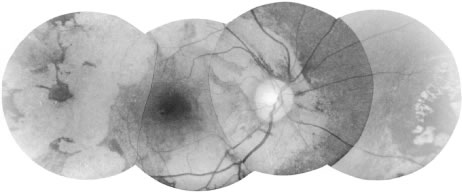

Chorioretinitis

Clinically, the most common change is a granular atrophy of the retinal pigment epithelium often with intraretinal dispersion of pigment from the pigment epithelium22,23 (Fig. 11). Although areas of severe atrophy are easy to see, milder forms may only be revealed by fluorescein angiography. Chorioretinal atrophy is common and is usually associated with retinal pigment clumping (Fig. 12). Well-defined, white plaque-like areas of subretinal fibrosis with neovascularization may occur in these areas. Each of these three changes—retinal pigment epithelial atrophy, chorioretinal atrophy, and subretinal fibrosis—represents an end stage of, or the structural change caused by, previous acute inflammation induced either by the local death of microfilariae or possibly by other immune mechanisms.

Fig. 11. Discrete areas of retinal pigment epithelial atrophy are one of the most common fundal changes seen in onchocerciasis. Usually they occur temporal to the macula, but they may occur elsewhere. When seen through a hazy cornea, they may need to be differentiated from drusen.

Fig. 12. Large area of chorioretinal atrophy, which shows characteristic sparing of the uveal region until late in the disease.

Areas of active inflammation in the retina can sometimes be seen.23 They appear as areas of posterior retinal edema that demonstrate leakage of retinal capillaries and veins on fluorescein angiography. Pale, ill-defined areas of swelling in the choroid may also occur. These also show leakage on fluorescein angiography and are believed to be choroidal granulomas. Transitory retinal pigment epithelial abnormalities have also been seen with DEC therapy.24 A severe retinal vasculitis may rarely occur.

It is the variation in prominence and the distribution of each type of change that leads to the wide variation in the final morphologic picture. The extent of involvement is not clearly related to the severity of the infection. The macular region is often spared until late in the disease.